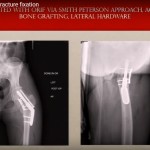

Femoral Neck Fracture fixation